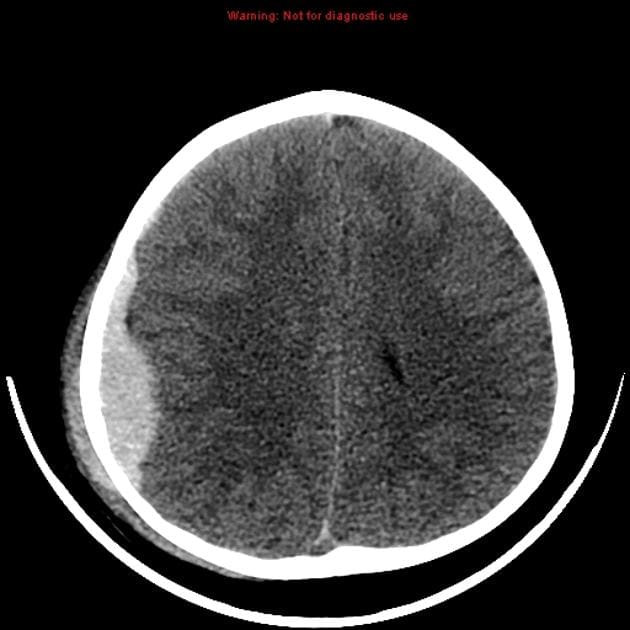

Гематома на МРТ головного мозга

Внутричерепное кровоизлияние — серьезная патология, требующая срочной помощи специалистов. Гематома опасна тем, что нарушает кровоснабжение мозга и повреждает нервную ткань из-за давления. Позднее обращение за медицинской помощью или неадекватное лечение может привести к смещению структур мозга из-за повышения внутричерепного давления, что угрожает жизни. Симптомы могут проявляться не сразу, что приводит к потере времени. При негативной динамике развития кровоизлияния шансы пациента на выживание снижаются, даже при грамотном лечении. Гематома вызывает сильную боль, а с увеличением внутричерепного давления могут появляться тошнота, рвота, нарушения сознания, судороги и очаговые неврологические симптомы (изменение размера зрачков, парезы, нарушения чувствительности, повышенные рефлексы и патологические знаки). Отрицательная динамика может привести к коме, нарушениям сердечно-сосудистой системы и остановке дыхания. Точная диагностика локализации процесса затруднена из-за быстрого изменения объема крови в очаге повреждения после травмы. Основной метод для быстрой оценки состояния мозга — компьютерная томография (КТ). Существуют различные классификации кровоизлияний в зависимости от локализации, источника и сроков. КТ позволяет определить характер гематомы, степень давности и вовлеченность окружающих тканей. Магнитно-резонансная томография (МРТ) помогает выявить тяжелые повреждения аксонов нервных клеток и оценить восстановительные процессы в отдаленные сроки. МРТ также позволяет дифференцировать ишемический и геморрагический инсульты, когда неясно, есть ли гематома в черепной полости.

Визуализация патологического процесса зависит от времени после травмы. В период от 24 до 72 часов после разрыва сосуда гематома может не отображаться на МРТ (ложно отрицательный результат). В первые сутки для оценки масштабов повреждений тканей и костей выполняют КТ, которая позволяет увидеть компоненты черепа и ушибы мозга (контузионно-геморрагические очаги). На основе результатов КТ нейрохирурги принимают решение о необходимости операции. Важна диагностика рентгеновскими лучами кровоизлияний, прошедших 12-72 часа. На КТ хорошо видны смещения костных отломков, их глубина, разрывы сосудов и масштаб вовлечения церебральных структур. МРТ может проводиться в экстренном порядке при госпитализации (например, при геморрагическом инсульте) до 24 часов после происшествия. В других случаях визуализировать кровь на МРТ удается только через три дня. Выявление причин гематом, постановка диагноза и неотложное лечение происходят в стационаре. В частных медицинских центрах МРТ выполняется по назначению врача, что позволяет оценить особенности гематомы (при хроническом процессе), последствия повреждений коры и осложнения, такие как гигрома и рубцово-атрофические изменения. Начиная с 7 суток после разрыва сосуда (в позднем подостром периоде), кровь на МРТ визуализируется лучше, имеет гиперинтенсивный сигнал на Т1 и Т2 взвешенных изображениях. При переходе в хроническую стадию кровоизлияние становится гипоинтенсивным (отображается темными участками).